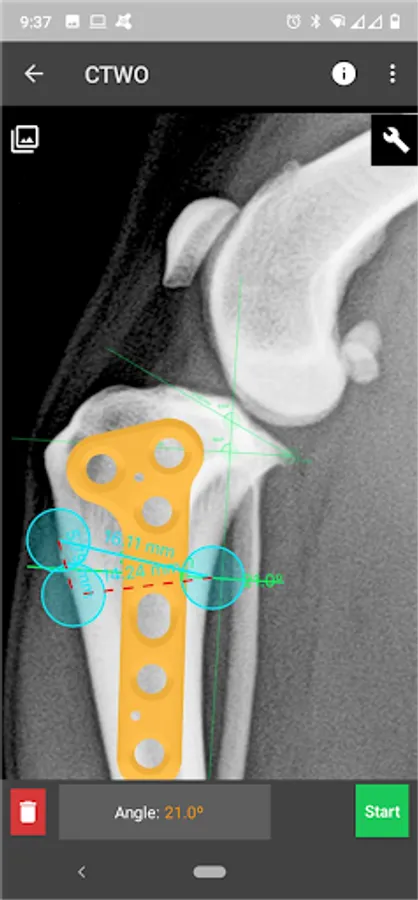

This is a useful tool for traumatology and orthopaedic surgical planning veterinary, including advanced techniques for treat canine anterior cruciate ligament (ACL) injuries (TPLO and CTWO).

3. Tools:

b) Radial measure/Circle draw.

c) Angle measure/Triangle draw.

e) Wedge cut, CTWO and angular osteotomies.

4. Catalogue of BETA Implants locking plates, in 2.0, 2.4, 2.7 and 3.5 sizes:

l) CTWO plates